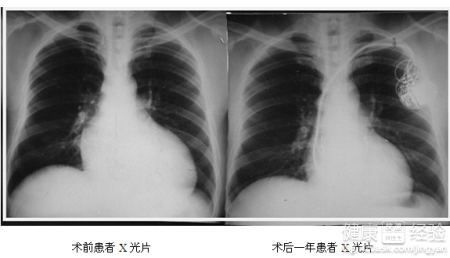

2擴張型心肌病的主要特征是心腔擴大,心肌收縮力減弱。研究表明,這種病極有可能是病毒感染引起的。而這種病往往以中年人居多,而且起病又比較慢,有的甚至長達10幾年,有時不易發現。